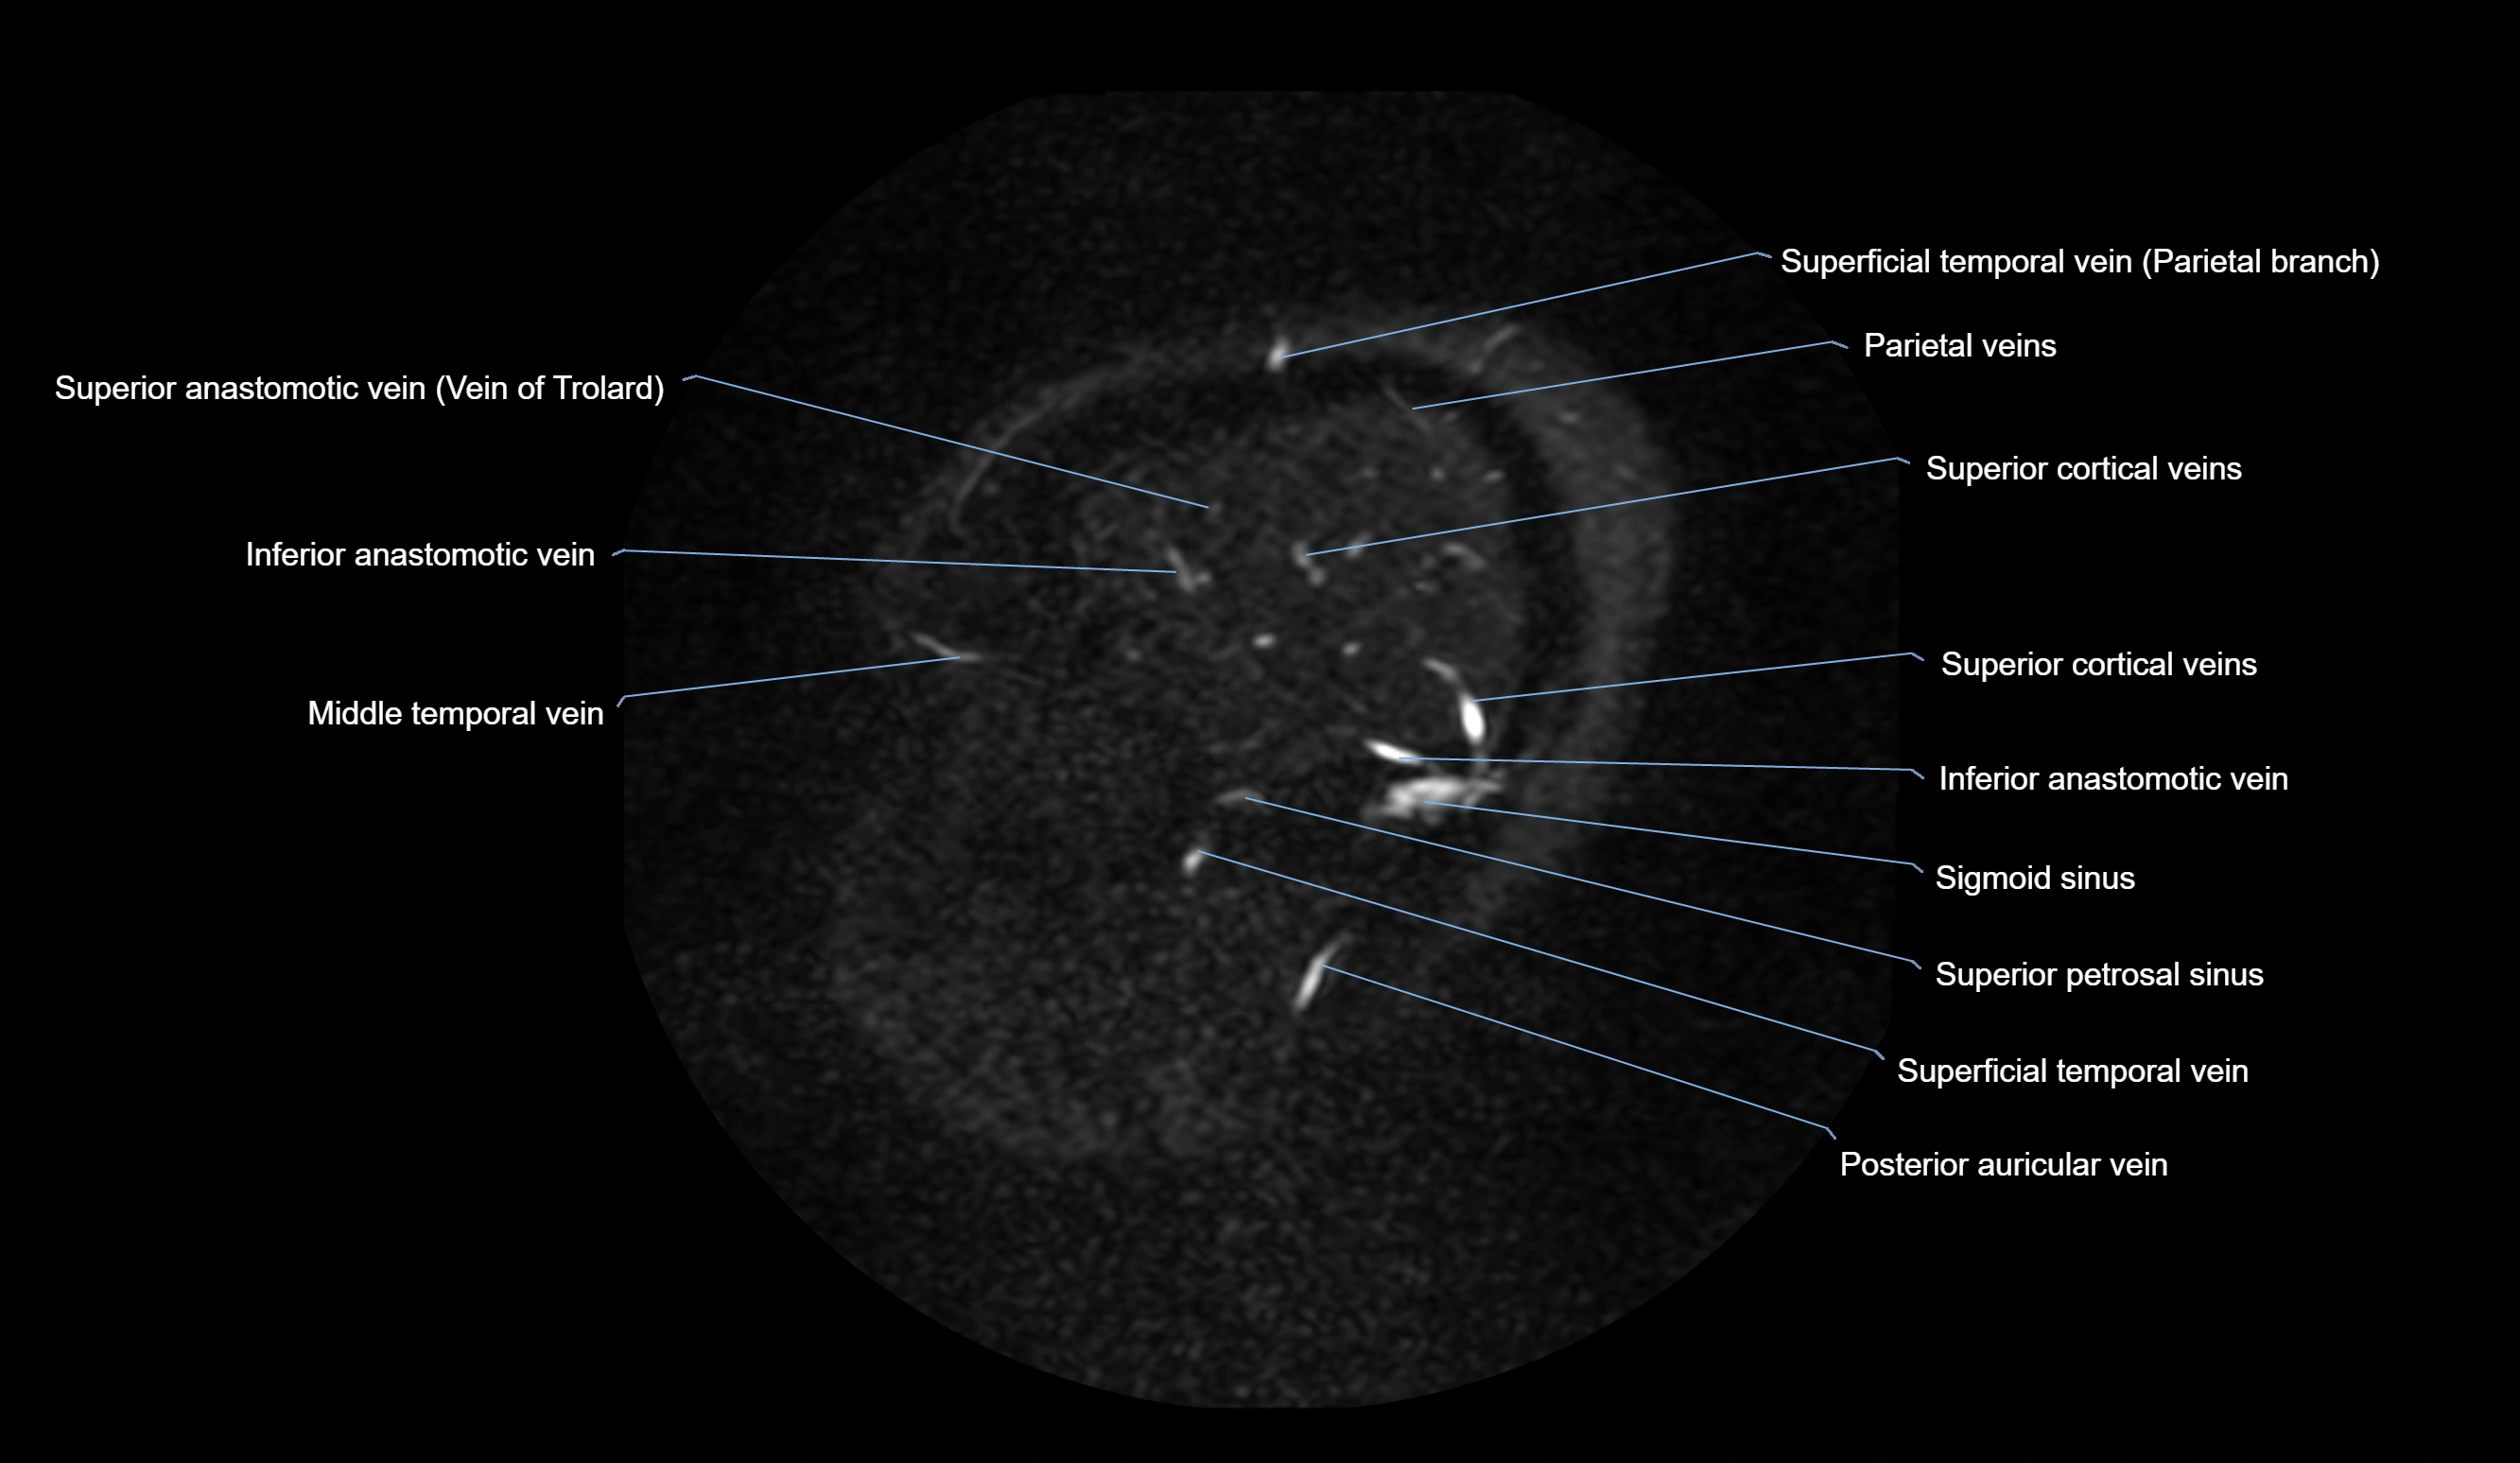

MRI Appearance

MR Venography (MRV):

• Time-of-flight (TOF) or contrast-enhanced MRV shows the angular vein as a bright enhancing venous channel

• Clearly demonstrates its continuity with the facial vein and superior ophthalmic vein

• MRV is highly useful in evaluating thrombosis, venous obstruction, or collateral venous drainage

MRI images

image